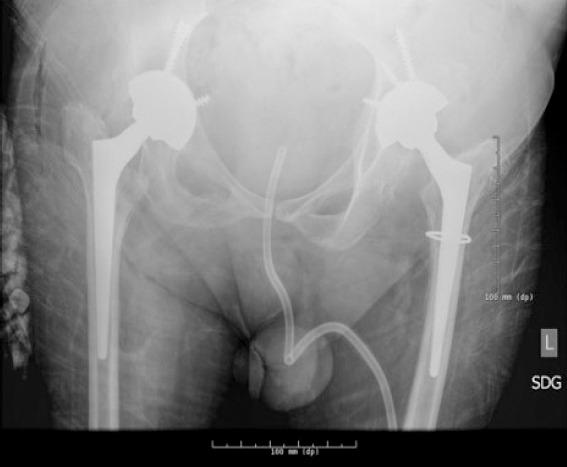

A 47-year-old man presented with bilateral hip and knee pain. Radiographs demonstrated valgus knee deformities with severe arthrosis and bilateral femoral head subluxation. The patient had a history of spina bifida with chronic lower extremity weakness and neurogenic bladder. He underwent staged bilateral instrumented knee arthrodesis and staged bilateral total hip arthroplasty (THA).

一名47岁男性因双侧髋部和膝部疼痛就诊。X线片显示膝外翻畸形伴严重关节炎和双侧股骨头半脱位。该患者有脊柱裂病史,伴有慢性下肢无力和神经源性膀胱。他接受了分期双侧器械辅助膝关节融合术和分期双侧全髋关节置换术(THA)。

这是首例报道的脊柱裂患者接受双侧器械辅助膝关节融合术的病例。这些患者的骨科护理较为复杂。通过器械辅助关节融合术和全髋关节置换术对有症状的膝部和髋部畸形进行手术矫正,可能会改善功能结局。